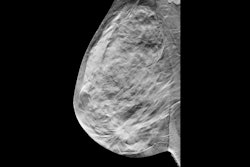

Sensitivity analysis showing the required relative reduction in breast cancer mortality for DBT screening to be cost-effective compared to DM screening, at a cost of €61 for a DBT-screening examination and cost-effectiveness threshold of €50,000/QALY.